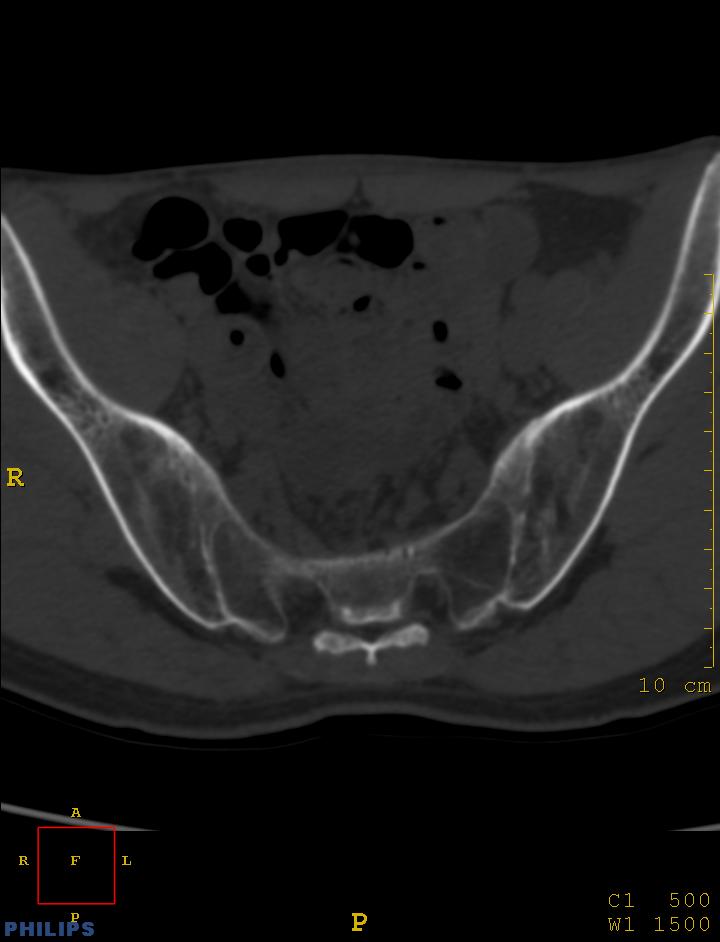

m,34岁,腰痛三年,腰椎活动度明显减低,x片示腰椎竹节样改变

双侧骶髂关节面融合;强直脊柱炎

双侧骶髂关节骨性融合,软骨下囊性变,结合脊柱竹节样改变,典型的强直性脊柱炎。